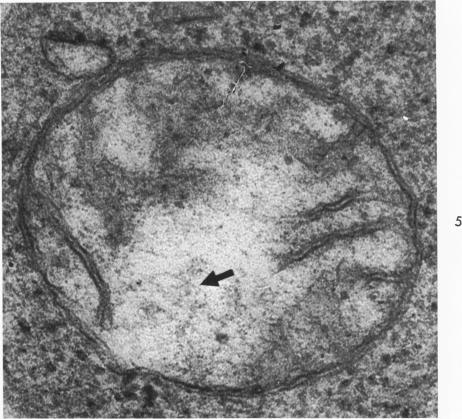

Quantitative and qualitative electron microscopic studies were performed on the leukemic cells of 3 patients with stem cell leukemia, 6 patients with acute lymphoblastic leukemia, 7 patients with acute monoblastic leukemia, 3 patients with acute myeloblastic leukemia and 7 patients with acute monomyeloblastic leukemia. Significant quantitative differences were noted between some of the leukemic cells in heterochromatin:euchromatin ratios, cell size, granules per cell, amount of endoplasmic reticulum and the number of polyribosomes. Qualitative abnormalities which were found in some cells of all the leukemic groups were observed. These abnormalities included nuclear pockets, deep nuclear indentations (usually not the stem cell), nucleosomes, dilated perinuclear spaces, centrioles located in nuclear pockets (not in the stem cell or lymphoblast), accumulation of microfibrils (greatest in the monoblast and myeloblast), disrupted mitochondria with virus-like particles (none in stem cells), smaller granules and mitochondrial DNA, glycogen, and myelin whorls. The presence of the smaller granules in disrupted mitochondria and the resulting clear areas is probably related to the deranged carbohydrate metabolism of these cells. The presence of virus-like particles within mitochondria may be extremely important, but requires much more investigation. Some of the above findings may offer clues to further investigation of the acute leukemic cell.

对3例干细胞白血病、6例急性淋巴细胞白血病、7例急性单核细胞白血病、3例急性粒细胞白血病和7例急性粒单核细胞白血病患者的白血病细胞进行了定量和定性电子显微镜研究。在一些白血病细胞的异染色质与常染色质比例、细胞大小、每个细胞的颗粒、内质网数量和多聚核糖体数量方面发现了显著的定量差异。在所有白血病组的一些细胞中都发现了定性异常。这些异常包括核袋、核深切迹(通常不是干细胞)、核小体、核周间隙增宽、位于核袋中的中心粒(不在干细胞或淋巴母细胞中)、微原纤维聚集(在单核母细胞和成髓细胞中最明显)、带有病毒样颗粒的线粒体破坏(干细胞中没有)、较小的颗粒以及线粒体DNA、糖原和髓鞘样小体。线粒体破坏时出现较小颗粒以及由此产生的透明区域可能与这些细胞紊乱的碳水化合物代谢有关。线粒体中存在病毒样颗粒可能极其重要,但需要更多的研究。上述一些发现可能为进一步研究急性白血病细胞提供线索。